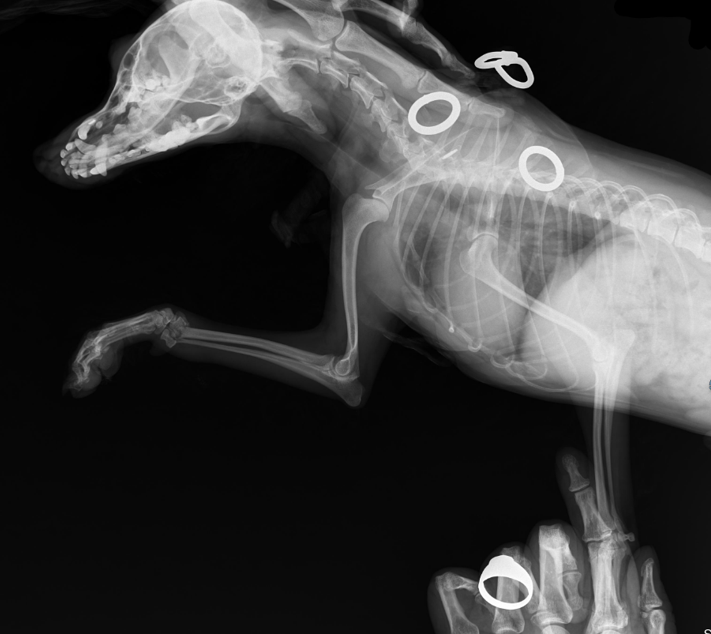

4 months old male kitten

Not using left front leg

diffuse soft tissue swelling of the left forelimb. The physis of the distal radius has a thin radiolucent line just proximal to it.

4 months old male kitten. presenting complaint Not using left front leg.

images from 4 weeks later:

4 weeks later: The soft tissue swelling is decreased.

Both proximal and distal growth plates of the radius are closed.

There is well defined new bone formation, especially at the proximal diaphysis of the radius.